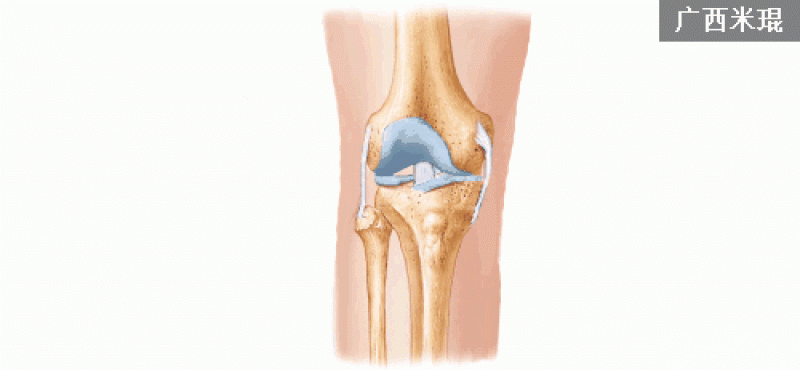

正常的膝关节进行MRI扫描时,不管任何一个序列,其骨髓信号一般T1WI呈均匀一致的灰色,T2WI及STIR呈均匀一致的黑色。

1.膝关节冠状位的正常MRI图像